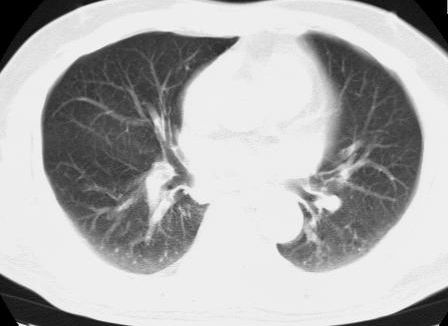

标题: CT15869:男性,71岁,因咳嗽而就诊,请讨论右上肺病变性质 [打印本页]

标题: CT15869:男性,71岁,因咳嗽而就诊,请讨论右上肺病变性质

患者,男性,71岁,因咳嗽而就诊,

典型的右肺中心性肺癌并纵隔淋巴结转移

右肺中心性肺癌并纵隔淋巴结转移可能性大!

考虑右肺中心性肺癌并右肺门及纵隔淋巴结转移。

1,右肺中心型ca,气管隆突旁淋巴结转移。

2,右膈明显抬高,建议肝脏扫描排除转移或原发灶。